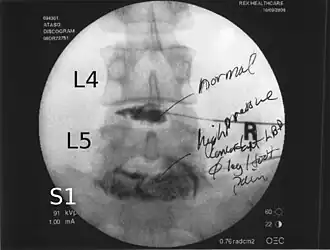

![]() Lumbar provocative discography showing a degenerated disc, L5-S1 with normal disc L4-L5 | |

Lumbar provocative discography (also referred to as "discography" or discogram) is an invasive diagnostic procedure for evaluation for intervertebral disc pathology. It is usually reserved for persons with persistent, severe low back pain (LBP) who have abnormal spaces between vertebrae on magnetic resonance imaging (MRI), where other diagnostic tests have failed to reveal clear confirmation of a suspected disc as the source of pain, and surgical intervention is being considered.

Spinal MRI is the imaging of choice to investigate the spine and intervertebral discs.[1] Meanwhile, lumbar discography is used to demonstrate degeneration and herniation of lumbar intervertebral discs by injecting a dye into the nucleus pulposus of the discs. The procedure is also used to reproduce pain back pain for those who have such symptoms. Lumbar discography is also used to access the response of a subject to anaesthetic injection. Other uses include suspected discogenic pain without radicular sign (pain travelling to lower limbs along a dermatome) and confirmation of normal intervertebral discs above and below a site before spinal fusion.[1] However, evidence supporting the usefulness of lumbar discography in recognizing intervertebral disc problems is limited.[1] There is no role for cervical or thoracic discography in diagnosing disc pathologies at the cervical or thoracic regions.[1][2]

Non-ionic contrast media such as iopamidol and iohexol are used.[1] Needles are inserted through the back into the disc near the suspect area, guided by fluoroscopic imaging. Fluid is then injected to pressurize the disc, and any pain responses are recorded.

A contrast agent is introduced, and after the procedure, a CT scan identifies leakage from the discs to identify any spinal disc herniation.